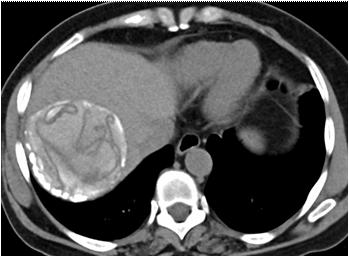

CT scan and/or MRI abdomen pelvis : CT Scan and/ or MRI abdomen pelvis was performed in 16 cases, both were accurately demonstrated the anatomical relationship of associated intra pelvic organs with surrounding fat and pelvic lymph nodes. CT Scan and/ or MRI abdomen pelvis clearly depicted prostatic utricle cysts in 3/3(100%) cases, intraprostatic abscess cavities in 2/2 (100%) cases, seminal vesicle cysts 2/ 2 (100%) and cystic connective tissue masses in 4/4 (100%). CT scan abdomen pelvis accurately demonstrated retro-vesical connective tissue solid masses in three cases. CT scan and/or MRI abdomen pelvis failed to differentiate accurate diagnosis in two cases (ejaculatory duct cyst and mullerian duct cyst with cystadenoma). However, MRI failed to differentiate between teratoma and haematoma. FNAC accurately demonstrates diagnosis in two cases of intraprostatic abscess (Fig 6).

mature teratoma and 3 were dermoid cysts). We were unable to clench the diagnosis in two cystic mass with our clinical and operative finding but confirm with HPE ie, Mullerian duct cyst with cystadenoma and inclusion cyst. Even after HPE report in one case of cystic mass suggestive diagnosis embryonic urogenital vestigial remnant? presacral meningocele but not confirmed.

Pre-sacral meningocele most frequently presenting as a presacral mass. It is an extension of the dura mater and arachnoid out of the sacral spinal canal into the retroperitoneal and intraperitoneal space through a congenital defect in the sacrum. Most of the patients presented with long standing constipation and urinary dysfunction. In case of constipation, the urinary dysfunction may be related to direct pressure on the bladder or may result from spinal cord tethering or sacral nerve root compression. Here we represent a 17-year-old male student with constipation for 5 years, episodes of ROU in the last one year & painless lump in the lower abdomen for 6 months. CECT and MRI abdomen showed a cystic mass in the pelvis, posterior to the bladder and posterolateral to rectum. On exploratory laparotomy confirm CECT finding with a fibrotic attachment to the posterior surface of the prostate. Mass was excised and sent for HPE. Biopsy of the specimen suggestive of embryonic urogenital vestigial remnants? Presacral meningocele? In 1971,